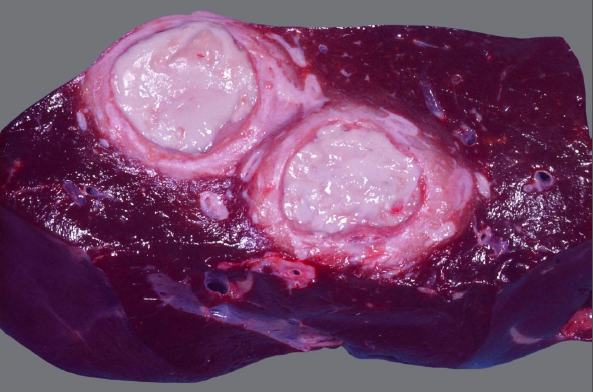

Rind, Leber: Hochgradige, chronische, oligofokale, eitrig – abszedierende Hepatitis

Beschreibung:

zwei gut umschriebene, weißlich – bekapselte und mit dickflüssiger, gelblich – grauer Substanz gefüllte Hohlräume von etwa 10cm ø

das umliegende Lebergewebe sieht verhältnismäßig physiologisch aus

Leberabszess Aufbau von innen nach außen

- Eiter

- pyogene Membran (2 Blätter)

- Kapsel

Ätiologie

aufgrund einer Omphalophlebitis, „omphalogen“ (Kalb, Fohlen, Ferkel): die Entzündung zieht an den

Gefäßen entlang in die Leber; Ätiologie: typische Eitererreger (Trueperella pyogenes, Streptokokken,

seltener E.coli oder Staphylococcus aureus)

Ruminitis – Leberabszess – Komplex (Mastrinder): Kohlenhydratreiches Futter > Pansenazidose >

Schleimhautläsionen > katarrhalische Ruminitis / Abomasitis > Bakterien im Pfortaderblut; Ätiologie:

Trueperella pyogenes

häufig in Kombination mit Fusobacterium necrophorum, diese führen aber eher zu Nekroseherden

Hauben – Fremdkörper: Durchspießen der Haube mit Einstich und Einbringen von Eitererregern in die

Leber (auch hier meist Trueperella pyogenes, Streptokokken o.a. klassische Eitererreger)

seltener hämatogene Einschleppung des Erregers (Bakteriämie), diese führt eher zu einer embolisch –

metastatischen Hepatitis

Hintergrundwissen/ Infektionsweg/ Pathogenese

klassischerweise einzeln oder in geringer Anzahl vorliegend

Entzündungscharakter geprägt von einer starken initialen Noxe mit eitriger Einschmelzung des Gewebes

bei einer funktionellen Immunantwort bildet der Körper eine Kapsel um den Defekt: eitrig – abszedierende /

apostematöse Entzündung

diese Kapsel reift mit der Zeit zu einer festen, bindegewebigen Abszesskapsel aus, die Entzündung im

übrigen Gewebe kann abklingen (ein Abszess ist damit das „Produkt“ einer chronischen Entzündung)

DD für Herde in der Leber: granulomatöse Hepatitis (Mykobakterien, Parasitengranulome),

Leberzellkarzinom, Leberzysten